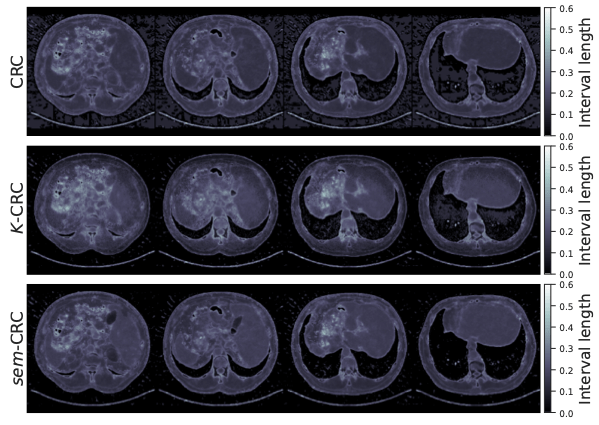

conformalized uncertainty maps

\(K=4\)

\(K=8\)

\[\mathbb{P}\left[\mathbb{E}\left[\text{fraction of pixels not in intervals}\right] \leq \epsilon\right] \geq 1 - \delta\]

Conformal guarantees for diffusion models

c.f. [Kiyani et al, 2024]

Teneggi, Tivnan, Stayman, S. How to trust your diffusion model: A convex optimization approach to conformal risk control. ICML 2023